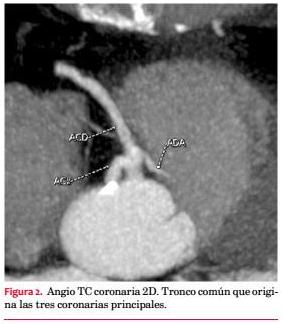

La CACG evidencia una arteria coronaria única, con origen en un ostium en el seno de Valsalva derecho y rápida división de un corto tronco común en arteria coronaria derecha (CD), descendente anterior (DA) y circunfleja (Cx) (figura 1). Tronco sin lesiones. CD dominante, con lesión severa en tercio distal. Descendente posterior con lesión severa ostial y en tercio medio. La DA, de fino calibre, tiene lesión suboclusiva en tercio medio y lesión severa distal. Cx sin lesiones. Gran ramo marginal presenta lesión severa proximal. Se realiza ATC de DA con implante de stent Minivision 2,0 mm por 2,3 mm sin incidentes.